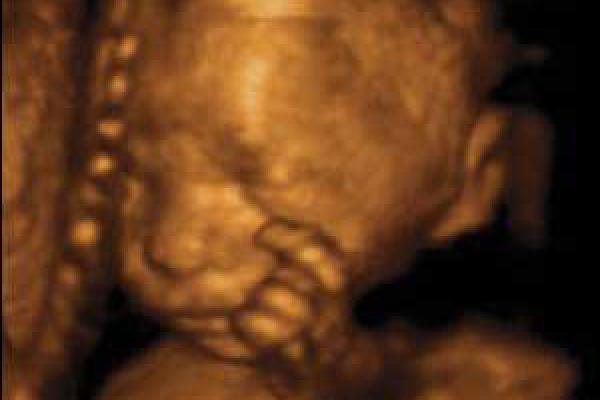

Il bambino ora prende quasi 200 grammi a settimana, pesa circa 1250 grammi e i suoi polmoni continuano ad esercitarsi nella respirazione. La testa cresce per fare spazio al cervello che ogni giorno vede nascere miliardi di nuovi neuroni, scalcia a più non posso ed è possibile contare i suoi movimenti per verificare il suo benessere e controllare che sia ben ossigenato. Per farlo, mettiti sdraiata su un fianco ogni giorno alla stessa ora, rilassati e concentrati su di lui, poi conta quanto tempo occorre al tuo piccolo per farsi sentire almeno dieci volte, conterai calci, pugni, singhiozzi e anche movimenti della testa e del sederino. La buona regola è che non servano più di due ore per arrivare a dieci.

Il bambino continua a crescere e ormai occupa quasi interamente lo spazio nell’utero.È possibile avvertire movimenti netti e precisi, al punto che potresti distinguere bene di quale parte del corpo si tratta, se la testa, il sederino o anche la schiena.

Il bambino è arrivato a circa 1400 grammi, è più cicciottello e la sua pelle è più liscia e rosea.Con le sue continue capriole, potrebbe trovare la posizione definitiva per la nascita.

Ora il piccolo pesa circa 1600 grammi, ogni giorno che passa mette su il grasso sottocutaneo e la pelle è meno rugosa, lo spazio disponibile è poco e i suoi movimenti sono meno “tellurici”.

L’utero è arrivato a circa 12 centimetri sopra la linea ombelicale trasversa e il piccolo pesa circa 1800 grammi ed è lungo circa 40 centimetri.